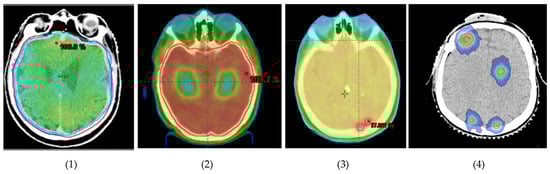

Over the years, brain radiotherapy has continued to evolve thanks to advances in radiation techniques including the use of intensity-modulated radiotherapy (IMRT), volumetric-modulated arc therapy (VMAT) and SRT (Figure 1).

Figure 1. Evolution of brain radiotherapy (from left to right): (1) WBRT; (2) HA-WBRT; (3) WBRT + SIB; (4) multiple-site SRT.